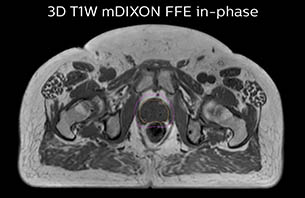

The TYKS MRI examination for generating the images for prostate MR-only simulation includes the standard sequences for MRCAT (Magnetic Resonance for Calculating Attenuation) generation, contouring and fiducial marker visualization. The total scan time for the RT planning sequences is 13 minutes. The ExamCard is customized with additional T2-weighted and DWI sequences for diagnostic purposes which makes total scanning time 26 minutes. The patients are imaged on a flat RT tabletop, using an Anterior MRI coil that is placed on a coil holder to avoid deforming body contours.

The MR images needed for RT planning are exported to the treatment planning system (TPS), where the MRCAT images are handled as a CT image set by the TPS, with no manual postprocessing required. Target and OAR delineation is performed using the T2-weighted images.

Using the mDIXON and 3D bFFE images, the RT planner marks the position of the nickel-titanium fiducial markers, and contours are transferred to the digitally reconstructed radiographs (DRRs). Reference image matching is based on these markers. “In the rare cases, where visualization of the fiducial markers fails, we do a CT to confirm their location,” Dr. Keyriläinen notes.

The 3D T1W FFE mDIXON sequence provides in-phase, water and fat images in one acquisition. Target and organs-at-risk are delineated on the 3D T2W TSE images. Prostate GTV is shown in orange, PTV in purple. The 3D bFFE sequence is used by the planner to mark the position of the fiducial markers (gold anchors) and contours are transferred to the digitally reconstructed radiographs (DRRs).